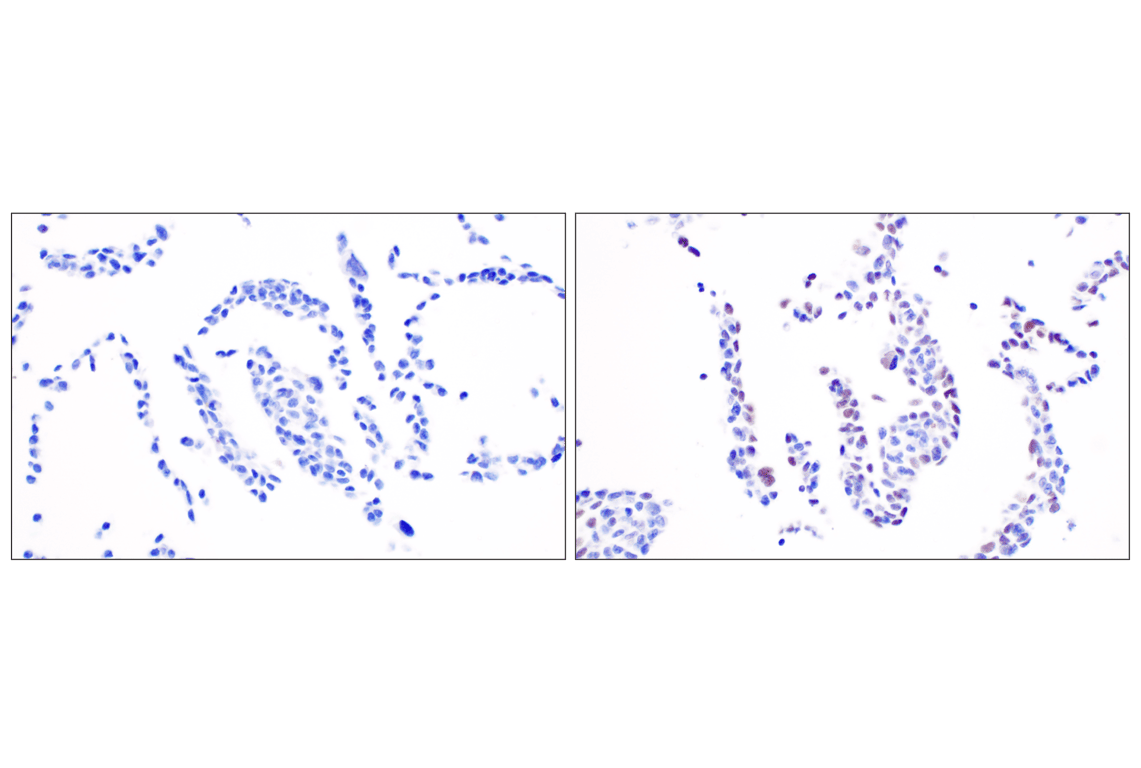

Colon 209: Immunohistochemical analysis of paraffin-embedded human adenocarcinoma of the colon, untreated (left) or lambda phosphatase treated (right), using Phospho-DNA-PKcs (Ser2056) (E9J4G) Rabbit mAb.

undefined Image 10: PhosphoPlus<sup>®</sup> DNA-PKcs (Ser2056) Antibody Duet